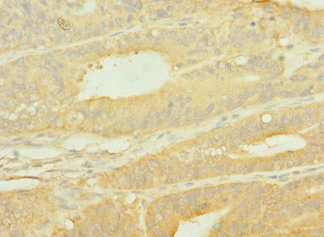

Immunohistochemistry of paraffin-embedded human endometrial cancer using CSB-PA622519LA01HU at dilution of 1:100